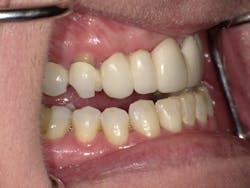

Left side prior to restorative treatment

Right side prior to restorative treatment; note the fractured bridge